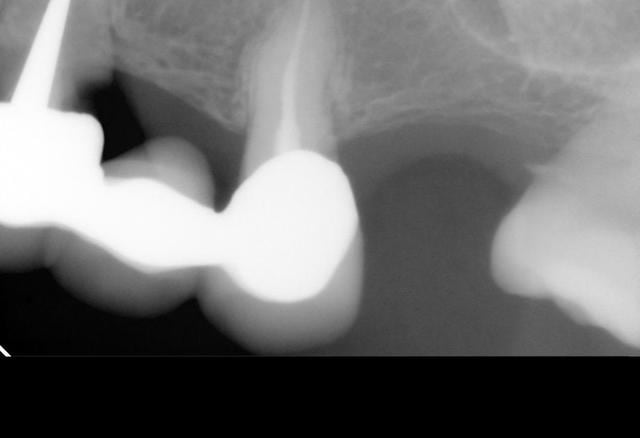

J'ai besoin d'avis éclairés pour une patiente dont voici la situation initiale:

- Femme de 83 ans qui consulte pour le rescellement de 44 avec 43 en extension collé au gros composite sur 42.

Voici le compte -rendu de mon bilan:

.Mandibule: 44/43 à refaire, 35 à 37 non remplacées, crête pas très épaisse derrière 34, problème paro (présence de tartre)

- pour la mandibule je pensais proposer un bridge 42 à 44 et implants secteur III mais avec un doute sur la faisabilité (possibilité de greffe? a définir avec le chirurgien)

+ doute sur la 47 (extraction à proposer d'emblée pour poser des implants là aussi ou je la préviens et on laisse ce coté tranquille pour le moment?)

Je vous met les radios et j'attend vos avis avec impatience.

sur ta radio RA secteur 1 la 16 semble limite en distal.

As-tu une radio plus centrée dessus?

bon, pour résumer en haut il ne te reste d’à peu près valable 12/11/21/25/27 (la 16 avec l'image inter-radiculaire est amha à mettre à la benne aussi...)